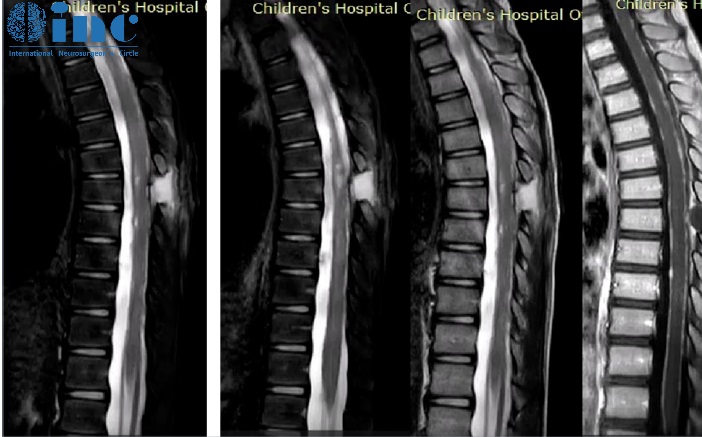

脊柱磁共振显示脑膜弥漫性强化,脑膜覆盖多处结节性病变,以及实质内病变和结节性小囊肿。

齐齐随即被转到神外科室,行椎管内病损切除术(T6-T7)。

术中发现硬脑膜异常增厚,下层为红色组织,并切除部分无明确边界的髓内病变。

从文献中提取的一些图像说明了刚才提到的情况:增强的蛛网膜的病理性增粗,肿瘤的多个结节状定位,相关的脑积水。大脑的非强化局灶性囊性病变是由血管周围间隙的局灶性扩大造成的,也是因为脑脊液循环受阻而扩大。